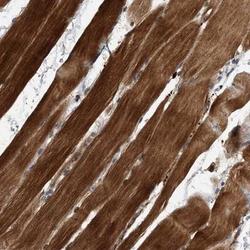

Immunohistochemistry

NBP1-90442 IHC